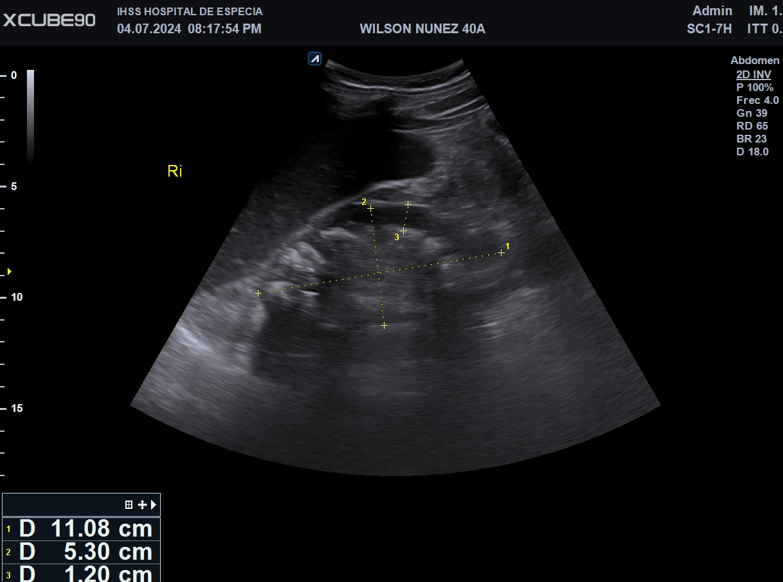

Imagen 3. Imagen de Ecografía escala 2D muestra la dilatación moderada del sistema colector derecho.

Identificando al menos imágenes, hiperecogénicas, ovaladas, de bordes circunscritos, proyectan sombra acústica posterior, avascular al Doppler color. Las cuales miden entre 0.8-1.0cm.